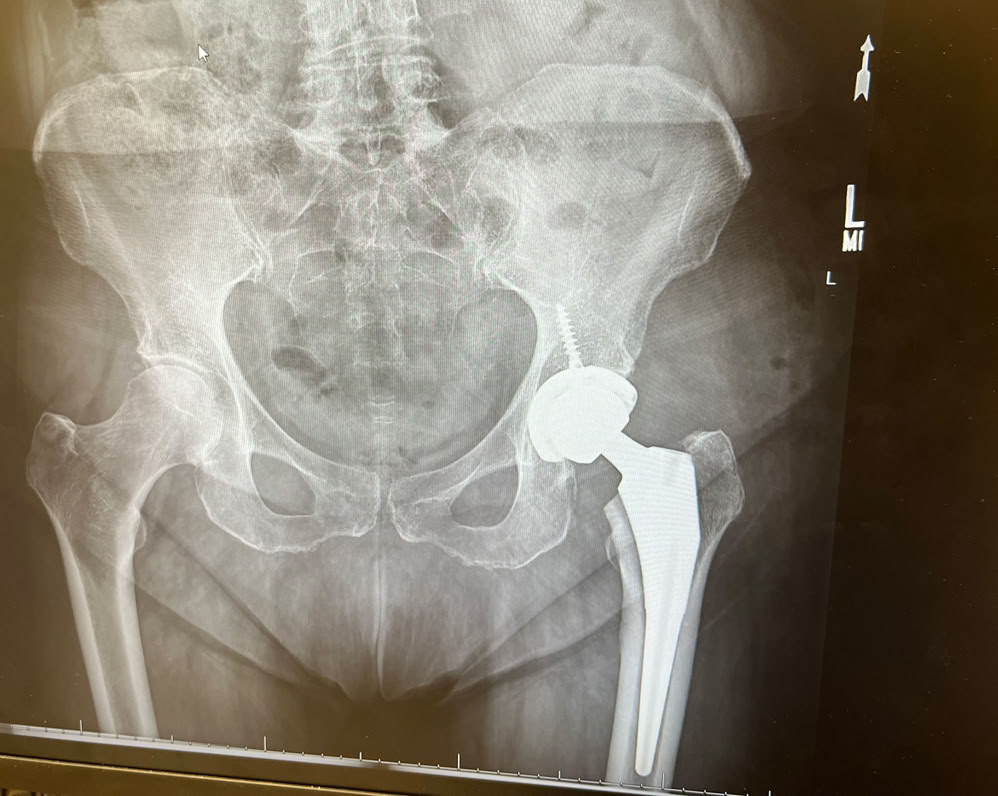

January found us heading to northern Minnesota to catch up with winter birding, something we’d not done for years.  February was Tom’s reverse shoulder replacement surgery (followed by months of physical therapy). April it was Carol’s turn - a new hip. And more PT. As we were once more living in Wisconsin, there was not need for an annual return visit. Instead we availed ourselves of farmers markets, supper clubs and seeing more of family. However, August required a trip west to Wyoming to attend granddaughter Cali’s outdoor wedding to her fiancé Daniel. September held two reunions. One for Carol’s family and the second Tom’s 60th high reunion. By the time November rolled around it was time for our bird tour to Northwest Argentina. Alas, owing to some unseen physical issues, Carol’s mobility prevented her from going on the tour. Shortly after Tom’s return from Argentina, it was time for his second reverse shoulder replacement surgery. The remainder of the year will be overshadowed by more physical therapy as we work our way through the holidays.